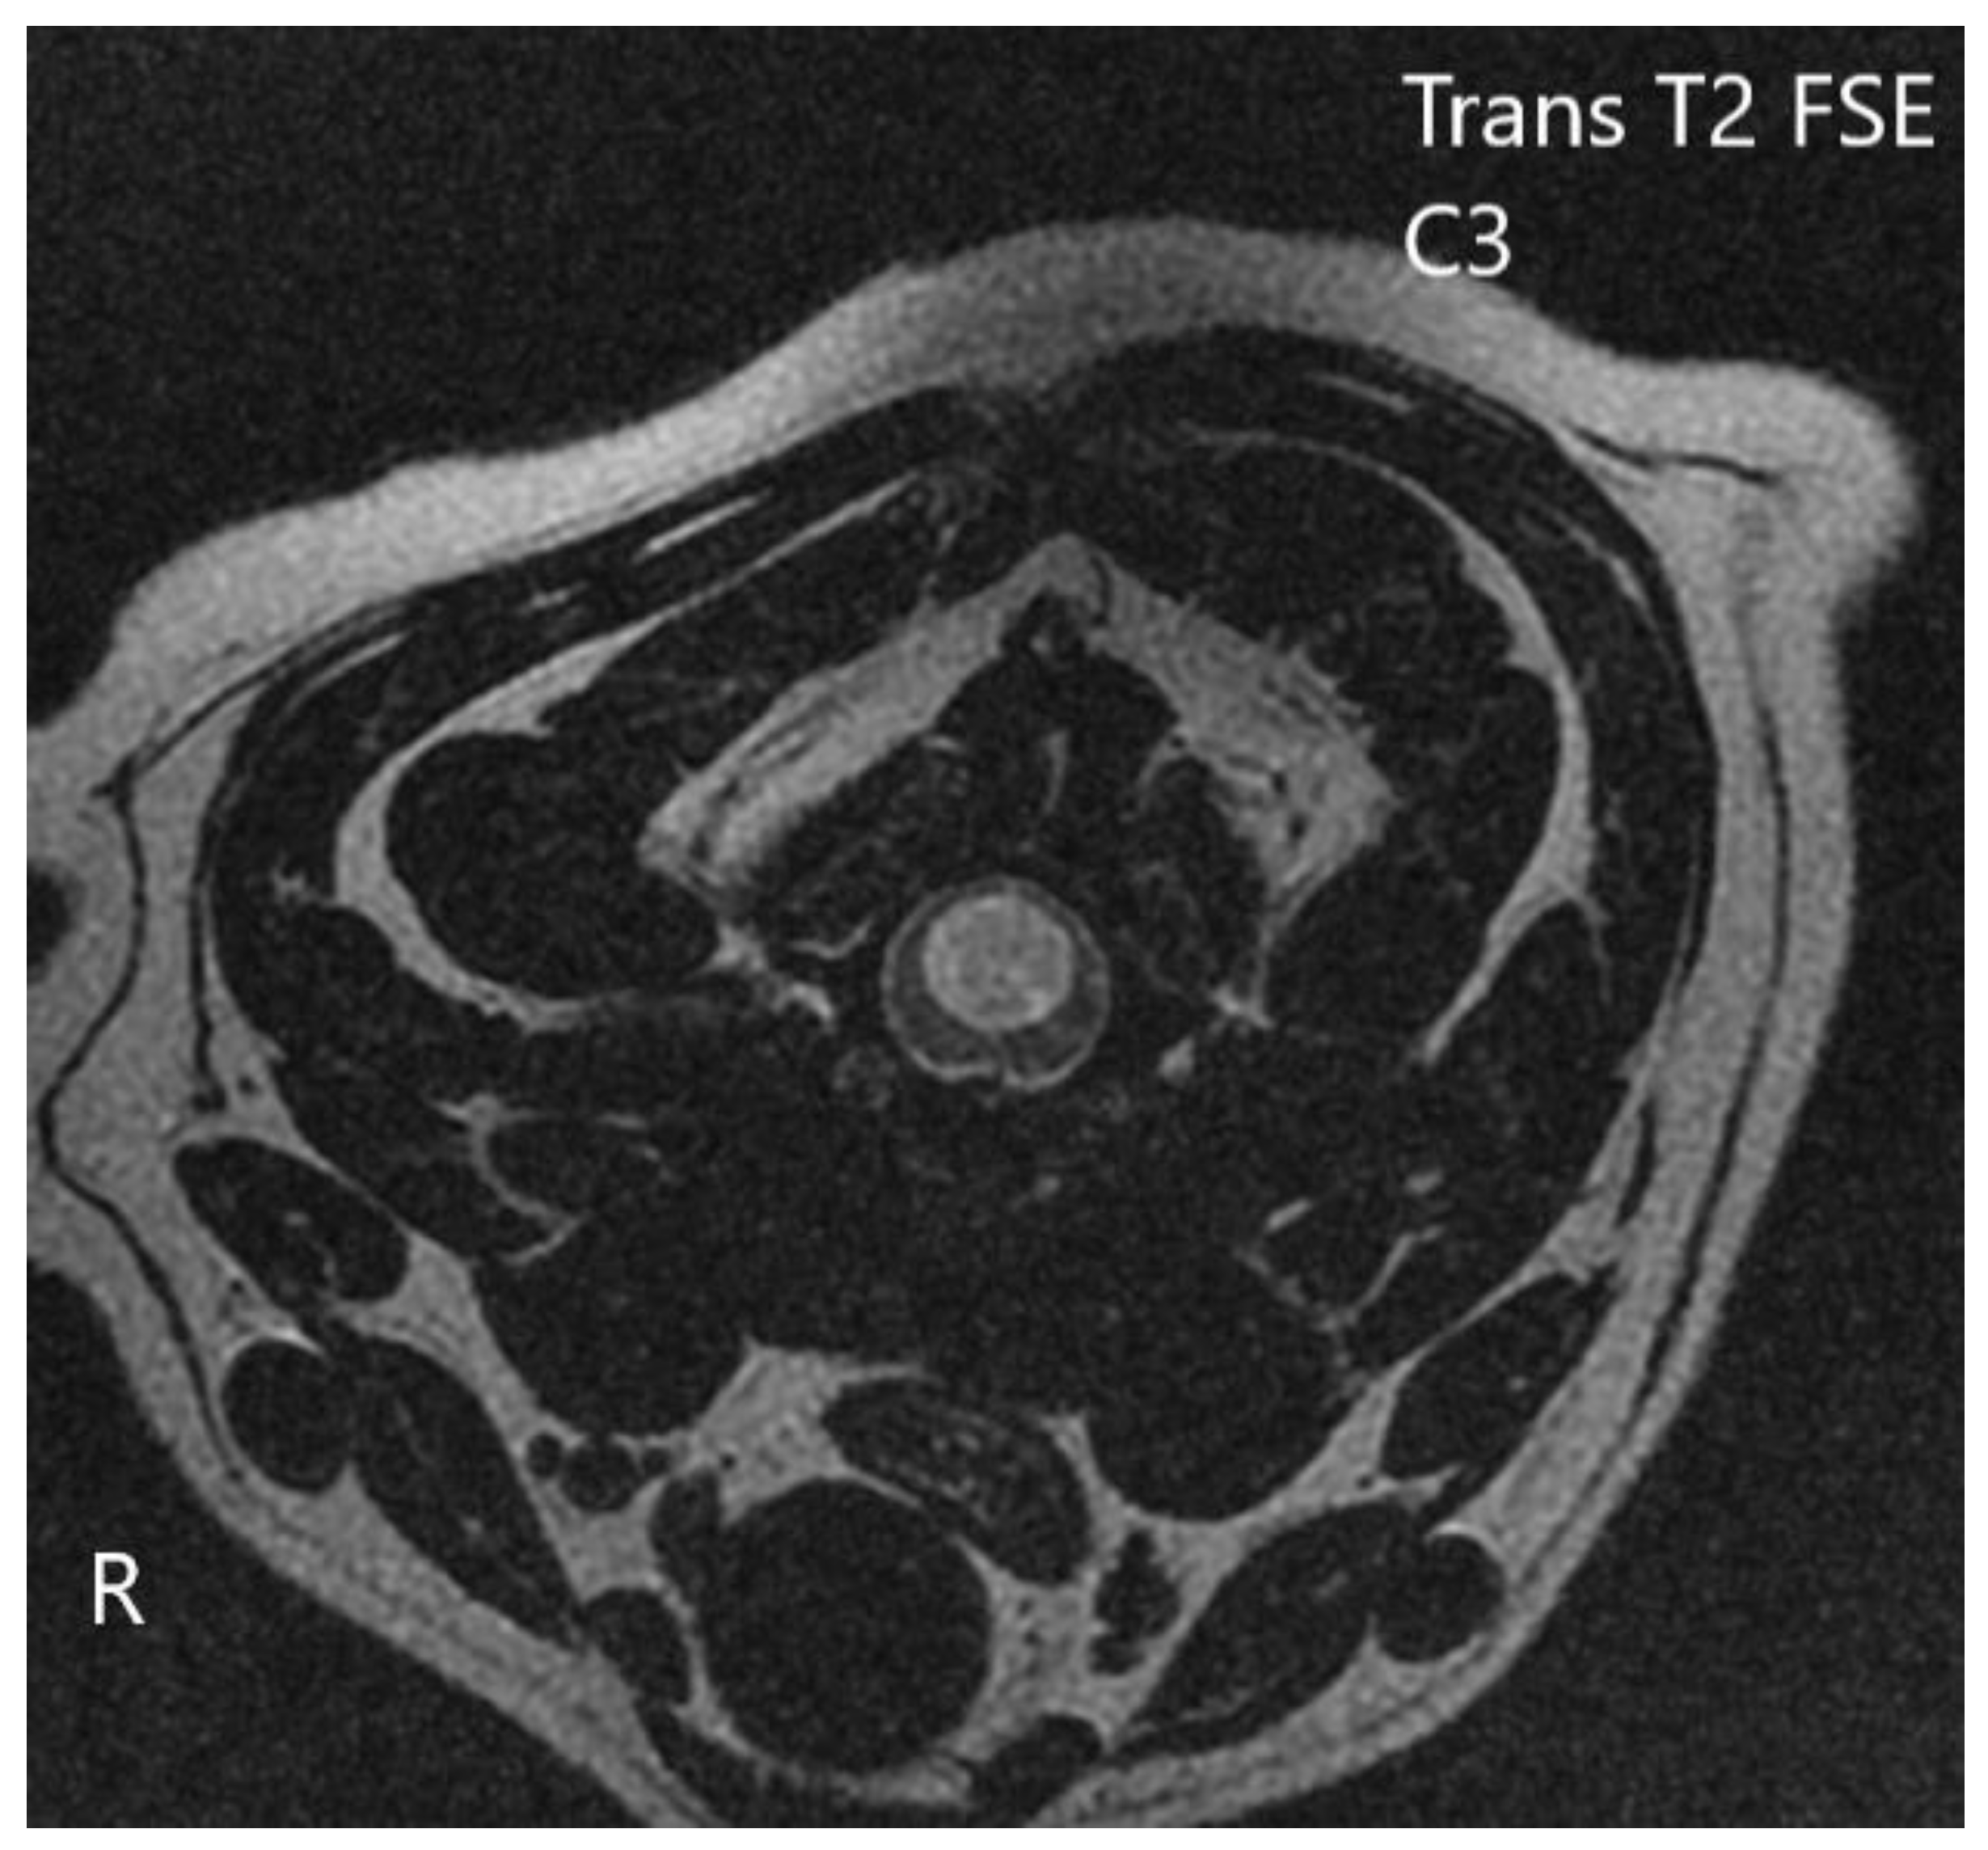

3.2. Diagnostic Imaging